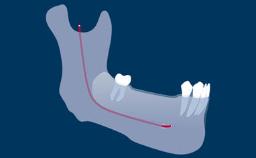

Prosthodontic Planning and Procedures

Principles of Computer-Aided Implant Planning

Learning Module